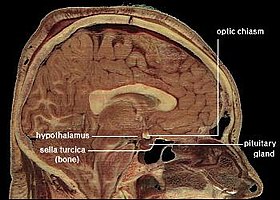

أظهرت نتائج ورقة علمية حديثة، لازالت قيد المراجعة، بأن حبوب منع الحمل قد تكون سببًا في انكماش منطقة ماتحت المهاد Hypothalamus في الدماغ بنسبة 6% مقارنًة مع اللاتي لم يتناولنَّها. هذه المنطقة مسؤولة عن تنظيم العديد من وظائف الجسم اللاإرادية مثل العواطف والنوم.

بدَت النتائج واضحة بعد التصوير؛ منطقة ما تحت المهاد أصغر بحوالي 6% في السيدات اللاتي تناولنَّ تلك الهرمونات. قد تبدو النسبة صغيرة جدًا، لكنها ليست كذلك في هذه المنطقة بالذات. لاسيما إن علِمنا أنها ضئيلة كحبة فاصولياء. نتيجة مهمة وبحاجة إلى تمحيص أكبر لمعرفة الأسباب.